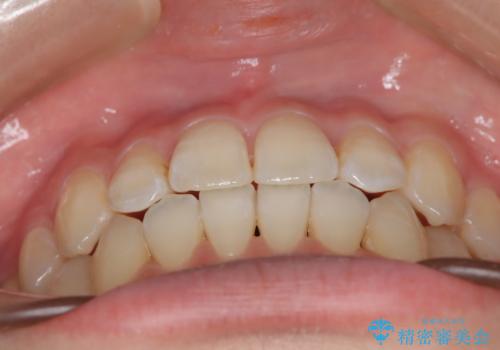

前歯のガタつき、下顎の前突感を治したい インビザライン矯正例

- 学生時代に矯正治療を経験されていましたが、その後の後戻りによる前歯の叢生・下顎の前突感を主訴に来院されました。叢生や口元の突出感が軽度であった為、非抜歯にて側方拡大やIPRを組み込んでインビザラインにて治療を計画しました。前歯部にクロスバイトがあり、治療途中に上顎前歯が下顎前歯を乗り越えなければならない時期もありましたが、患者様の協力的なマウスピース装着もあり、良好な配列を達成しました。上下左右の親知らずは、当院にて矯正開始前に抜歯しました。